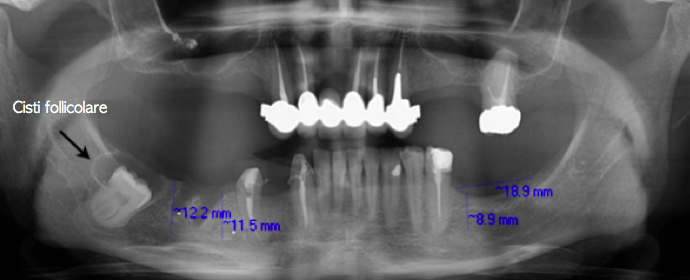

I denti del giudizio inclusi non di rado sono la causa di formazioni cistiche (Cisti Follicolari o Dentigera).

La cisti dentigera è la lesione non infiammatoria più comunemente riscontrabile nei mascellari e rappresenta circa il 20% di tutte le cisti mascellari.

Per definizione, la cisti dentigera deve essere associata alla corona di un dente ritenuto o incluso, occasionalmente a un dente sovrannumerario o a un odontoma. La cisti si forma attorno alla corona del dente incluso e, quando la cisti è completamente formata, la corona si trova all’interno della cavità cistica mentre le radici sono situate al di fuori di essa. Lo sviluppo di questa cisti è caratterizzato da un periodo di latenza, che si contraddistingue per un lento accrescimento durante il quale la sintomatologia dolorosa è assente. Al periodo di latenza segue lo stadio di deformazione ossea, in cui la cisti erode la corticale dell’osso, ovvero la parte più densa ed esterna dell’osso, fino a sollevare i tessuti molli.

Le cisti follicolari di una certa dimensione possono determinare notevoli spostamenti, blocco dell’eruzione e riassorbimenti radicolari degli elementi dentali adiacenti.

Si noti la cisti follicolare che avvolge la corona del dente e la distruzione dell’osso causata dalla cisti stessa. Dalla TAC risulta che il nervo alveolare passa tra le radici del dente del giudizio inferiore di sinistra.